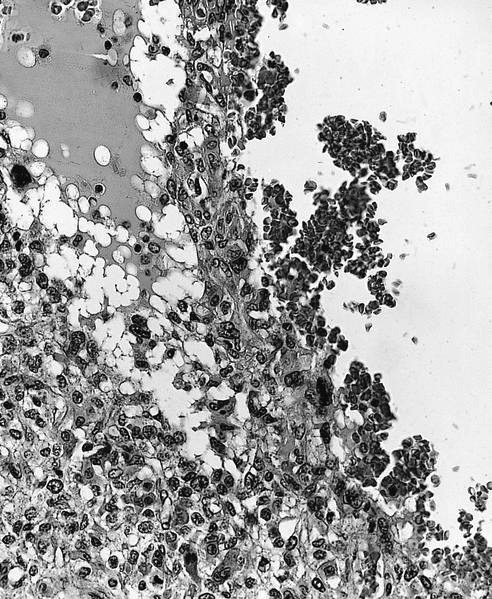

Microscopic (histologic) images

Contributed by Jesse Hart, D.O., Borislav A. Alexiev, M.D. and AFIP

A 12 year old girl has a 10.5 cm intramedullary mass in the distal femur, which was resected (see gross and microscopic images). High power views demonstrate bland spindle cells. Which of the following is most accurate regarding this tumor?

Practice answer #1

A. Most likely, genetic abnormality is amplification of the MDM2 gene. The tumor is a low grade central osteosarcoma.